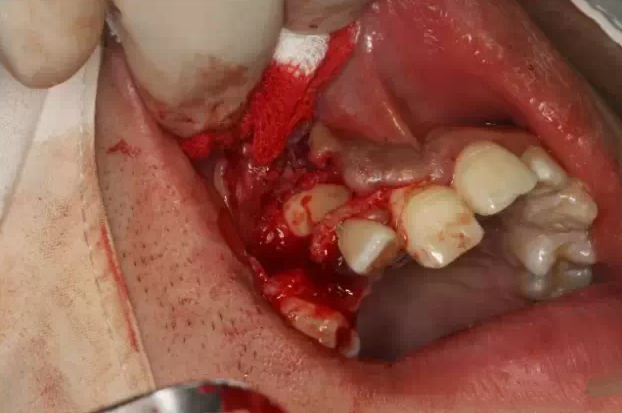

暴露13唇面

QQ圖片20150730095139.png

清理牙冠唇側(cè)部分軟組織

QQ圖片20150730095158.png